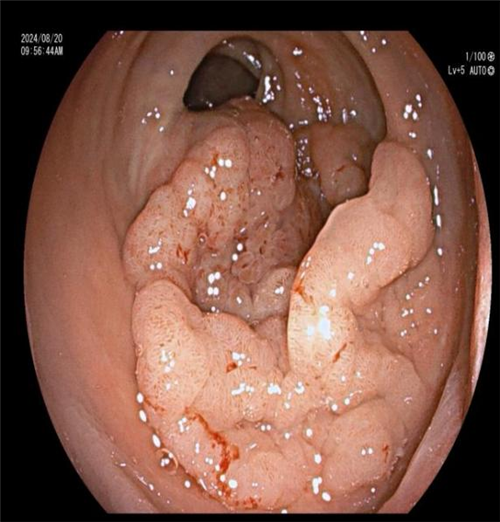

近日,一位患者因 “反复上腹胀痛、纳差 1 年余” 入住我院普外二科(胃肠外科)。入院肛检发现直肠后壁有大块颗粒样增厚区,CT 提示直肠壁增厚。进一步肠镜检查后,内镜下见直肠约 6*5cm 侧向发育型息肉,下缘距肛门仅 2.5cm,活检病理为绒毛状管状腺瘤。

科主任曾春辉在与患者及家属商讨手术方式时,了解到患者极度排斥外科手术,因其病变位置特殊,距离肛门仅 2.5cm,开刀恐难以保住肛门,患者表示宁愿不做手术也不愿生活质量低下。尽管病变巨大且位置特殊,内镜手术难度大、风险高,已超出常规 ESD 手术范畴,但曾主任毅然决定挑战技术极限。他在全麻下为患者施行 “内镜下直肠下段侧向发育息肉 ESD 术(隧道内镜技术)”,手术顺利完成。